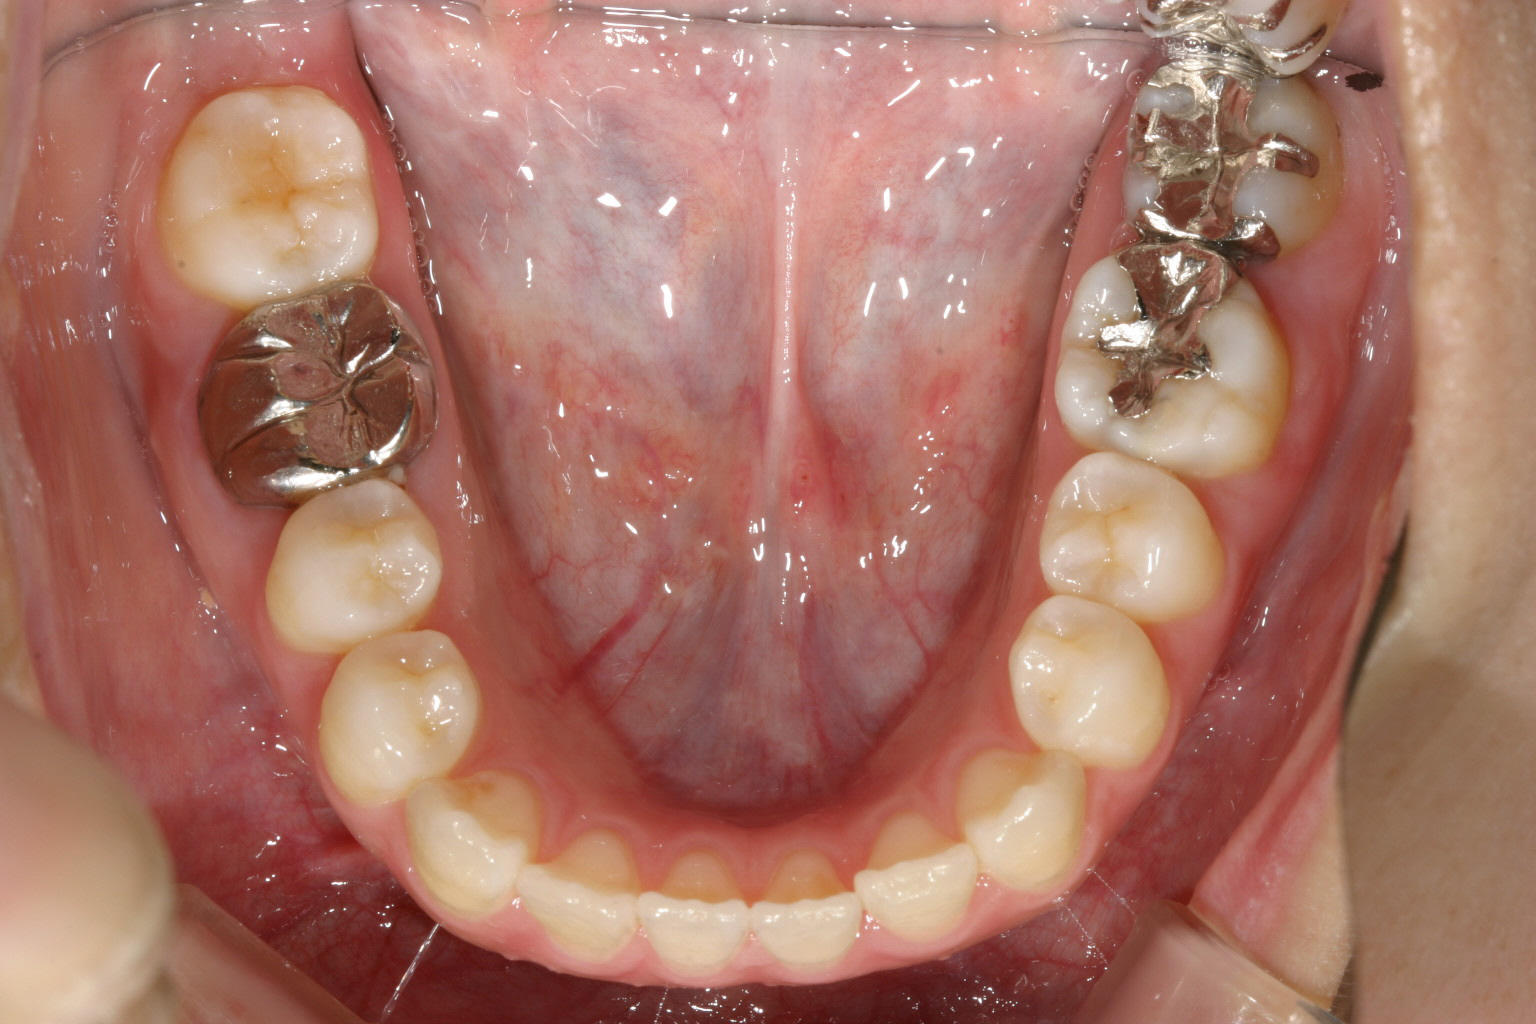

下顎も上顎と同じく犬歯間幅径が狭く叢生になってます。

下顎も半年経つとかなり綺麗に並んでいます。

下顎もバッチリです。

全体的にアーチが尖ったV字歯列をされてましたのでU字に改善させ、また臼歯部を圧下させる方法により前歯を咬合させました。